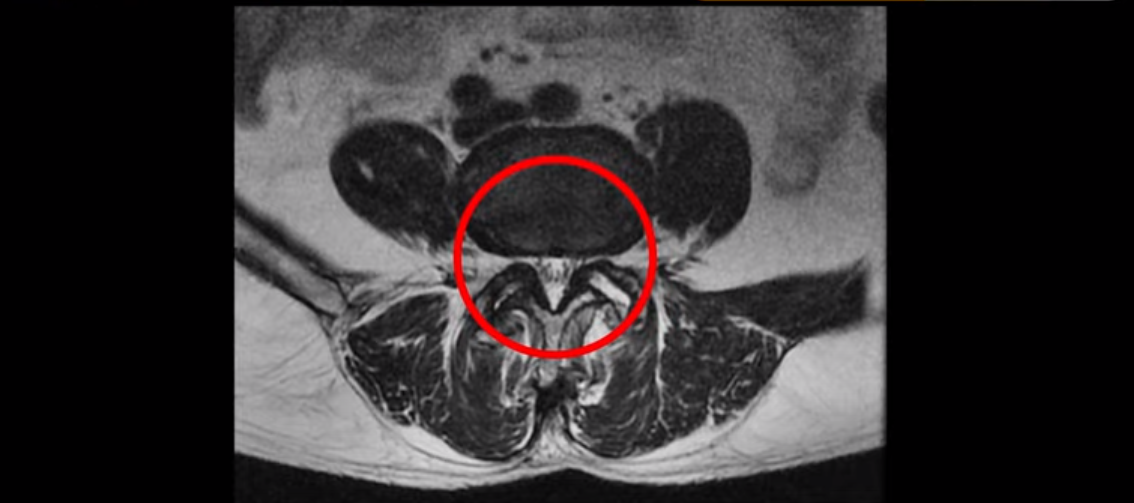

MRI를 보면 척추 여러 마디가 퇴행되어 있고

척추관도 좁아져 있고

특히 왼쪽 신경가지가 빠져나가는 4번 5번, 5번 1번 추간공들이 많이 좁아져 있습니다.